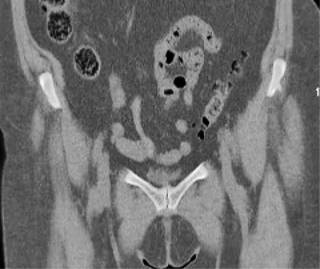

Posteriormente se solicitó una tomografía computarizada (TC) de pelvis en el que se confirmaban los cambios degenerativos (Figuras 4 y 5) y una resonancia magnética que mostraba hallazgos de inflamación en las sínfisis compatibles con osteítis de pubis, asociados a edema de la musculatura adyacente. Ambas pacientes estuvieron realizando sesiones de fisioterapia y toma de antiinflamatorios no esteroideos (AINE) y corticoides con escasa mejoría. La infiltración de bupivacaina junto con corticoide fue el tratamiento más efectivo, pero pasados los dos meses la clínica, se reprodujo y se planteó en ese momento la opción quirúrgica. Las puntuaciones en la escala visual analógica (EVA) previamente a la cirugía fueron de 8 y 9, respectivamente.

Figura 5: Tomografía computarizada corte axial: misma paciente en la que se aprecia osteofito medial.